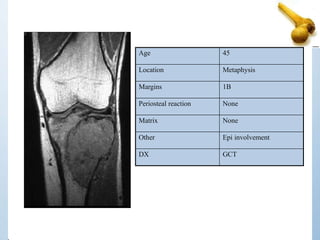

Age 45

Location Metaphysis

Margins 1B

Periosteal reaction None

Matrix None

Other Epi involvement

DX GCT